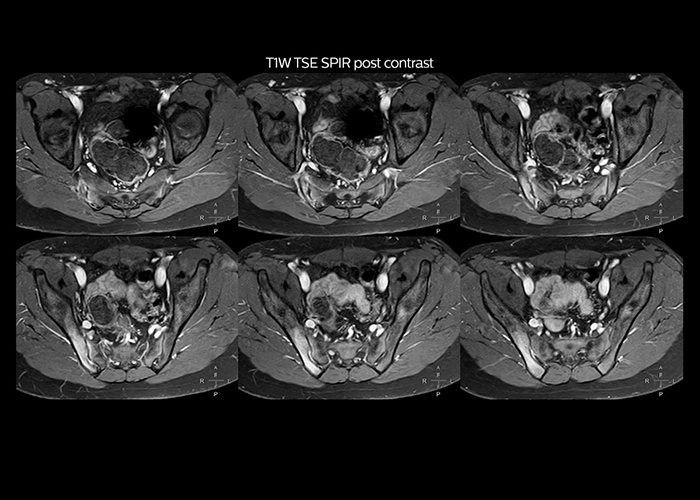

“To avoid coil changes we plan examinations of similar anatomies back to back, such as head and spine. Multiva helps us here a lot because coils don’t need to be changed frequently. Moreover, thanks to parallel imaging technology and 16-channel HeadSpineTorso and 8-channel MSK coils we are able to achieve excellent image quality. In this way Multiva helped us to increase both image quality and productivity.”

“Most important, Multiva satisfies our clinical imaging needs very well,” says Mr. Tuna. “Many features of Multiva have become similar to the Ingenia system. Even in more complex imaging such as abdominal and cardiac, the image quality and performance of Multiva is better than we expected. General surgeons and physicians from our hospital’s internal medicine department prefer to refer to us because of this.”